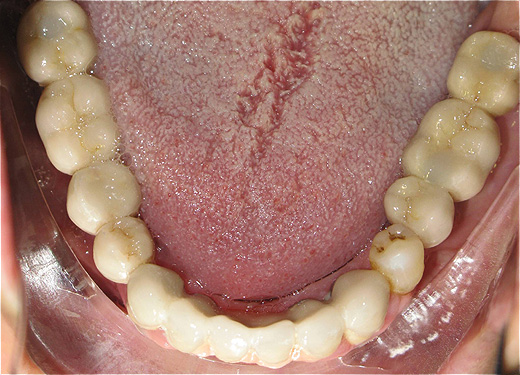

Resultado de colocação de implante dentário na Clínica São Filinto

Caso 1 - Implante imediato após extração do dente fraturado (dente 11) e implante imediato

![]() |